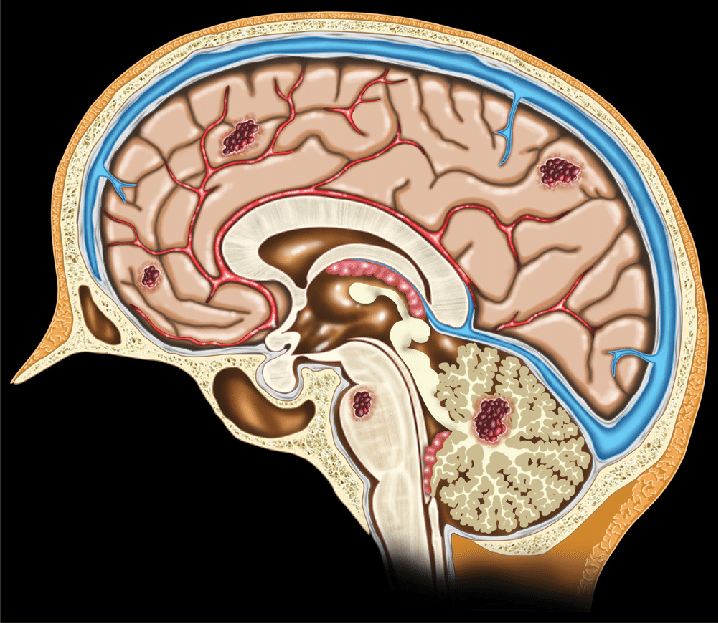

Мр картина венозной ангиомы левой гемисферы мозжечка - 96 фото